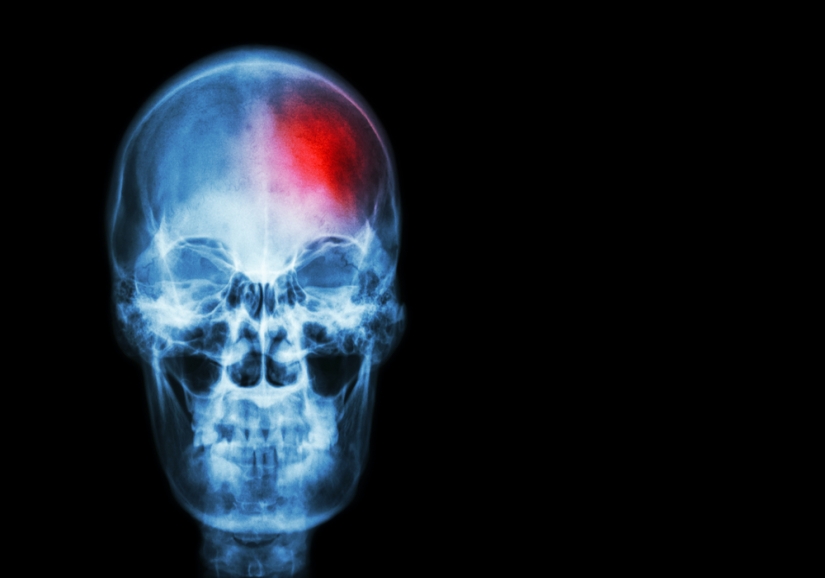

O acidente vascular cerebral (AVC) ou acidente vascular encefálico (AVE), também chamado apoplexia, congestão cerebral ou, como o povo diz, “derrame”, designa comprometimento na irrigação sangüínea do cérebro, às vezes grave, que pode causar morte instantânea ou diferentes seqüelas, como paralisia mais ou menos extensa.

No “derrame” ocorre bloqueio arterial ou hemorragia, que leva à perda súbita de consciência e comprometimento de uma parte do cérebro. Este comprometimento pode, em casos mais graves, representar degeneração, amolecimento e morte de uma parte do cérebro. Entretanto, em acidentes menos comprometedores, é possível a recuperação das funções cerebrais. O tamanho e a localização da área afetada, que deixa de ser irrigada normalmente, determinarão a gravidade do ataque. E por falar em irrigação, convém frisar que, se a obstrução é importante, total ou quase total, o perigo é maior. Até o perigo de hemorragia é, neste caso, iminente. Entretanto, se houve apenas obstrução parcial, o ataque é como um alarme do organismo, que tenta chamar a atenção para o perigo de obstrução mais grave.

Conforme a região do cérebro afetada podem ser danificadas diferentes funções. Se o acidente ocorre, por exemplo, nos núcleos cerebrais que comandam os movimentos do braço esquerdo, ou da perna direita, estes membros poderão ficar paralisados. Às vezes, a lesão acontece no núcleo de comando da visão, podendo ocorrer cegueira; no núcleo de comando da audição, podendo ocorrer surdez, e assim por diante. Se os comandos do raciocínio e da memorização são afetados, o paciente pode sofrer comprometimentos mentais mais ou menos sérios, como alienação e perda de memória.